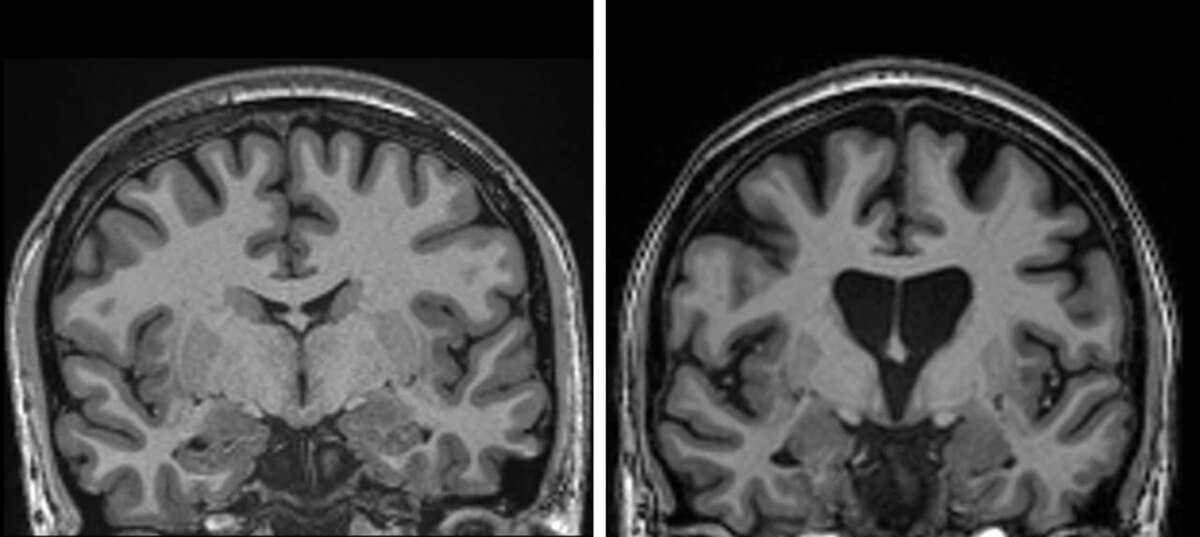

Это одна из самых страшных болезней мозга: что-то вроде Альцгеймера и Паркинсона, только в одном флаконе. Болезнь генетическая, то есть люди рождаются с ней, и всю их жизнь в мозге копятся дефектные белки. На фотографиях видно, как мозг постепенно умирает: отверстие в центре увеличивается в десятки раз, а число извилин буквально уменьшается. Примерно к 60 годам больной теряет память, не может двигаться, говорить и даже глотать. Никаких лекарств от этой болезни нет, так что пациенты неизбежно умирали.